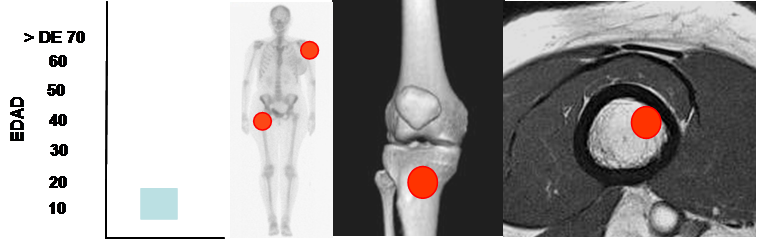

Se encuentra entre 5 y 15 años y puede ser asintomático o presentar dolor, por una fractura patológica. (35). (Fig 139).

Compromete la metáfisis de los huesos largos, con predominio del húmero y fémur proximal. (35, 38). (Fig 134).

Fig 134. Quiste óseo simple.

Mayor frecuencia entre los 5 y 15 años. Predominio en la parte proximal de los huesos largos.

Lesión metafisiaria, de ubicación excéntrica.